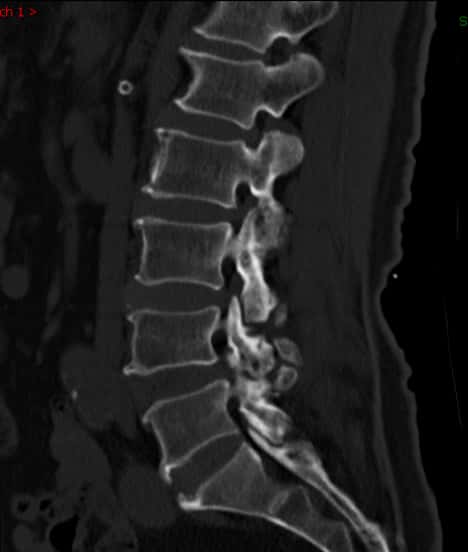

腰椎侧位片子看腰4/5有轻度滑脱。

断面可见明显的增生改变,提示腰椎不稳定。

核磁上可见椎4/5间孔狭窄,神经根受压变形。

核磁上可见椎间孔狭窄,神经根受压变细。